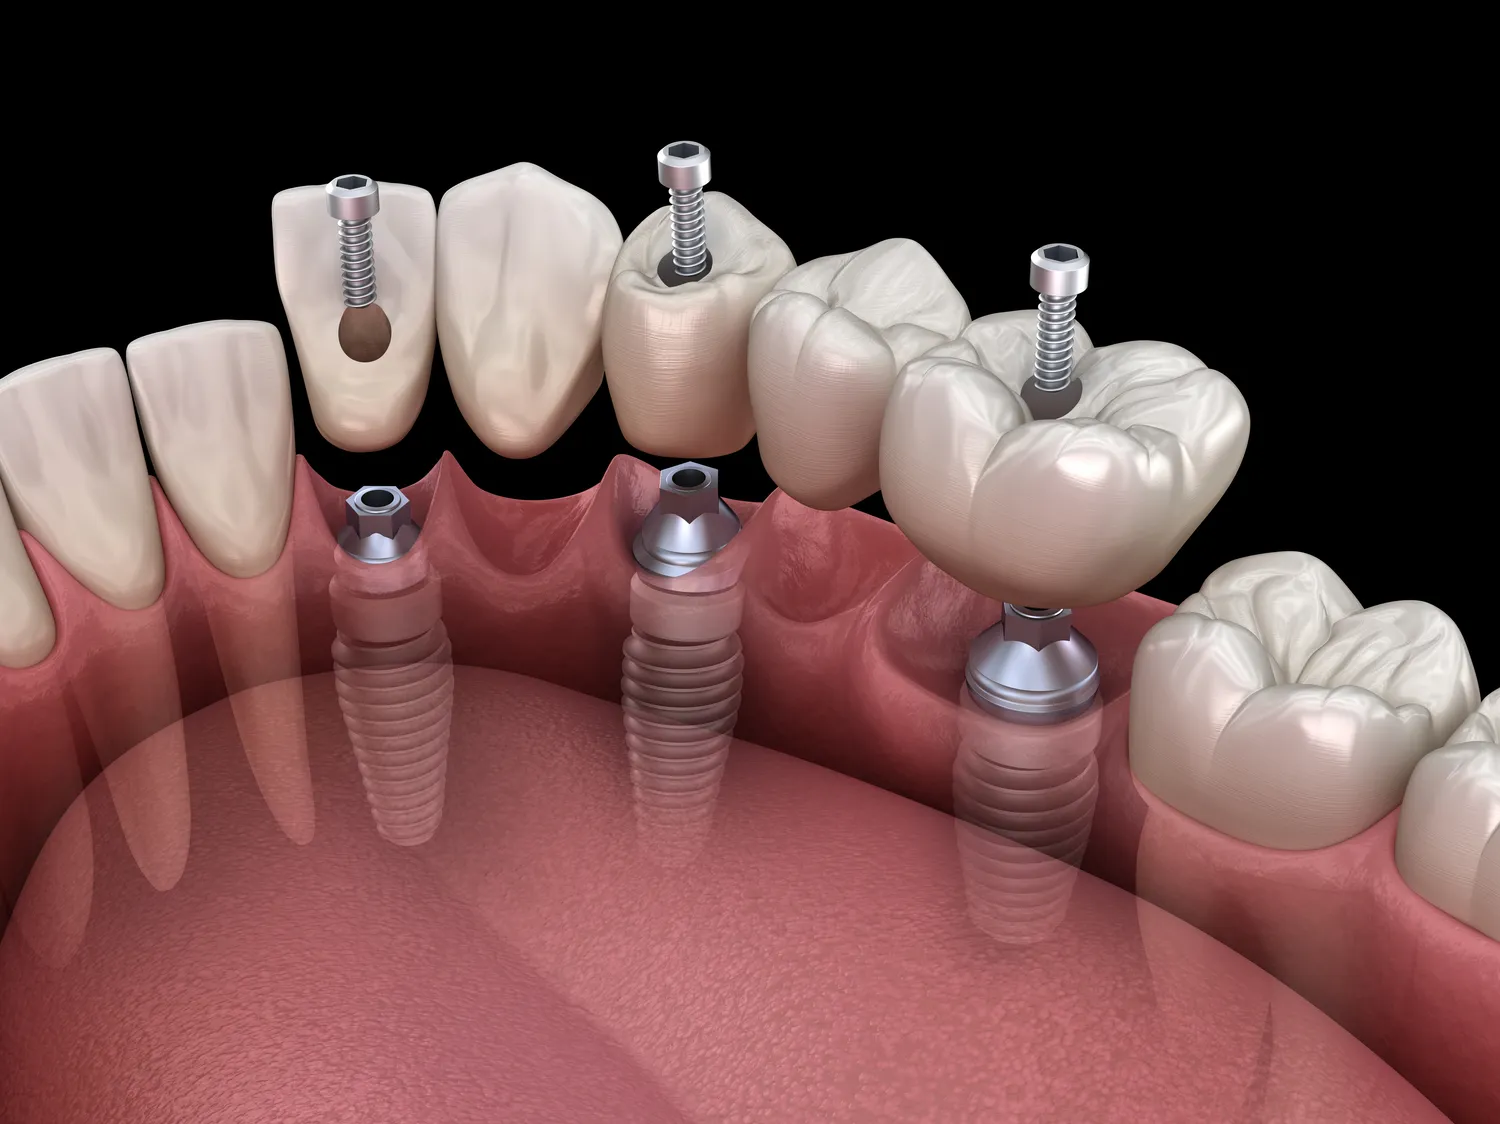

Implanty zębowe to coraz popularniejsza metoda uzupełniania braków w uzębieniu, a ich koszt w Warszawie może się znacznie różnić w zależności od wielu czynników. Przede wszystkim warto zwrócić uwagę na rodzaj implantu, który chcemy zastosować. Na rynku dostępne są różne systemy implantologiczne, które różnią się jakością materiałów oraz technologią produkcji. Ceny implantów mogą zaczynać się od około trzech tysięcy złotych za jeden implant, ale mogą również sięgać nawet sześciu czy siedmiu tysięcy złotych za bardziej zaawansowane rozwiązania. Dodatkowo, należy uwzględnić koszty związane z zabiegami chirurgicznymi, które są niezbędne do wszczepienia implantu. W Warszawie ceny takich zabiegów wahają się od kilkuset do kilku tysięcy złotych, w zależności od skomplikowania przypadku oraz doświadczenia lekarza. Warto również pamiętać o kosztach dodatkowych, takich jak zdjęcia rentgenowskie czy konsultacje specjalistyczne, które mogą być wymagane przed przystąpieniem do zabiegu.

Proces zakupu implantów w Warszawie rozpoczyna się od wizyty u stomatologa, który przeprowadzi dokładną ocenę stanu zdrowia jamy ustnej pacjenta. Na podstawie wykonanych zdjęć rentgenowskich oraz badań lekarz oceni, czy pacjent kwalifikuje się do zabiegu wszczepienia implantu. Następnie zostanie przedstawiony plan leczenia wraz z kosztorysem, który uwzględnia wszystkie niezbędne etapy procedury. Warto zadać pytania dotyczące używanych materiałów oraz technologii, aby mieć pewność co do jakości proponowanych rozwiązań. Po zaakceptowaniu planu leczenia następuje etap przygotowań do zabiegu, który może obejmować dodatkowe badania czy zabiegi przygotowawcze, takie jak ekstrakcja zębów lub regeneracja kości. Sam zabieg wszczepienia implantu odbywa się w znieczuleniu miejscowym i trwa zazwyczaj od jednej do trzech godzin. Po zakończeniu procedury pacjent otrzymuje zalecenia dotyczące pielęgnacji oraz kontrolnych wizyt pooperacyjnych.

Decydując się na uzupełnienie braków w uzębieniu, pacjenci mają do wyboru kilka różnych metod, a każda z nich ma swoje zalety i wady. Implanty dentystyczne są jedną z najnowocześniejszych i najbardziej trwałych opcji dostępnych na rynku. W porównaniu do tradycyjnych mostów czy protez ruchomych, implanty oferują większą stabilność oraz naturalny wygląd. Mosty wymagają szlifowania zdrowych zębów sąsiadujących z brakującym zębem, co może osłabić ich strukturę i prowadzić do dalszych problemów stomatologicznych. Z kolei protezy ruchome mogą być niewygodne i wymagać częstego dostosowywania oraz wymiany. Implanty nie tylko eliminują te problemy, ale także wspierają strukturę kości szczęki, co zapobiega jej zanikanie po utracie zęba. Jednakże koszt implantów jest znacznie wyższy niż w przypadku mostów czy protez, co może być istotnym czynnikiem dla wielu pacjentów. Warto również zauważyć, że proces wszczepienia implantu jest bardziej skomplikowany i czasochłonny niż w przypadku innych metod uzupełniania braków w uzębieniu.

W ostatnich latach rozwój technologii związanych z implantologią znacząco wpłynął na jakość oraz efektywność zabiegów wszczepienia implantów dentystycznych w Warszawie. Jednym z najnowszych osiągnięć jest zastosowanie cyfrowego planowania zabiegów chirurgicznych, które pozwala na precyzyjne zaplanowanie lokalizacji implantu oraz minimalizację ryzyka powikłań. Dzięki technologii CAD/CAM możliwe jest również wykonanie indywidualnych ortez czy koron protetycznych na podstawie skanów 3D jamy ustnej pacjenta, co zapewnia idealne dopasowanie i estetykę. Innym innowacyjnym rozwiązaniem jest zastosowanie materiałów biokompatybilnych, które wspierają proces gojenia się tkanki kostnej oraz zmniejszają ryzyko odrzutu implantu przez organizm pacjenta. W Warszawie coraz więcej klinik oferuje także możliwość korzystania z technologii laserowej podczas zabiegów chirurgicznych, co pozwala na szybsze gojenie oraz mniejsze uszkodzenia tkanek otaczających implant. Dodatkowo nowoczesne systemy implantologiczne umożliwiają stosowanie różnych typów implantów dostosowanych do indywidualnych potrzeb pacjentów, co zwiększa skuteczność leczenia i komfort użytkowania.